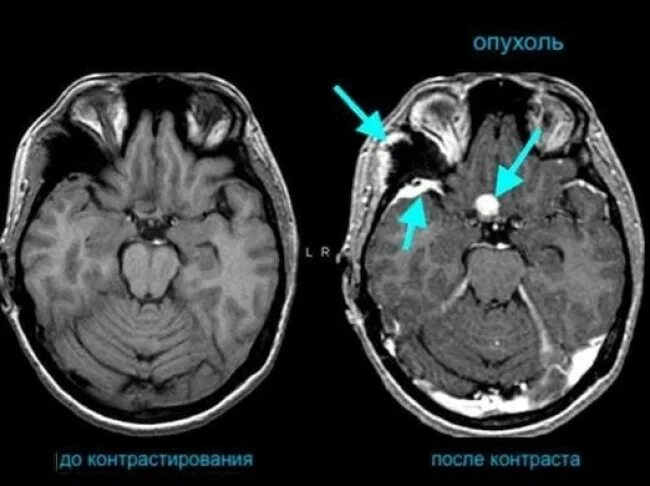

Плохо после контраста кт